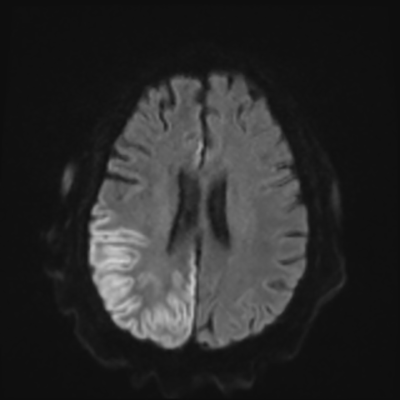

You come back the next day and see how things are going. The patient's electrographic record has shown a moderate encephalopathy (diffuse slowing, disorganization) with frequent right posterior quadrant delta slowing. Based on this result, and an adequately improved clinical examination, you give the okay to proceed with obtaining an MRI of his brain. This is shown below.

MRI brain (DWI)